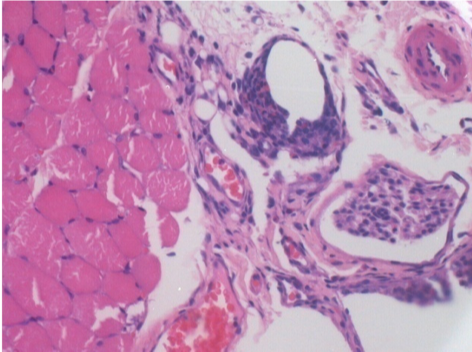

1 mese dopo Iniezione Endopeel

Scatola Nr 3

1 mese dopo Iniezione 0.1ml di Endopeel nel muscolo pretibiale destro ( Dx) .

Che cosa viene visualizzato in nero nella figura Sx : 100x-Giorno30 non é una necrosi come potrebbe immaginare un dilettante.

In effetti, 4 conclusioni devono essere prese in considerazione

- un artefatto di colorazione

- un`assenza di necrosi

- un`apoptosi

- un processo biorigenerativo

Sx : Controllo-100x-Giorno30

Dx:100x-Giorno30

Dx :400x-Giorno30